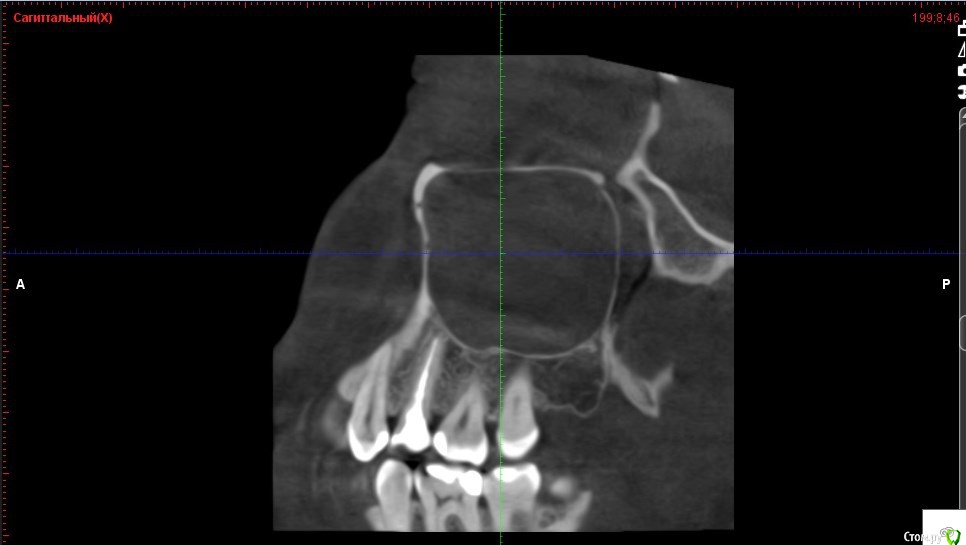

Verasss Опубликовано 8 октября, 2016 Автор Поделиться Опубликовано 8 октября, 2016 КТ от 08.09. Извините, что в таком виде, надо менять ОЗУ. Ссылка на комментарий

DmitrySH Опубликовано 8 октября, 2016 Поделиться Опубликовано 8 октября, 2016 В таком виде КТ малоинформативно. Но гайморита нет. Ссылка на комментарий

Verasss Опубликовано 28 октября, 2016 Автор Поделиться Опубликовано 28 октября, 2016 Добрый вечер! Ещё раз попытаюсь прикрепить скриншоты КТ от сентября. Если качество совсем не устраивает, подскажите, пожалуйста, какие сделать снимки?К сожалению, программа не позволяет вывести снимки на полный экран и заскриншотить в более хорошем качестве. Ссылка на комментарий

Verasss Опубликовано 28 октября, 2016 Автор Поделиться Опубликовано 28 октября, 2016 еще снимки Ссылка на комментарий

Verasss Опубликовано 28 октября, 2016 Автор Поделиться Опубликовано 28 октября, 2016 и еще Ссылка на комментарий

Verasss Опубликовано 23 ноября, 2016 Автор Поделиться Опубликовано 23 ноября, 2016 Сделала ещё 1 кт, спустя почти 2,5 месяца после первого. Посмотрите, пожалуйста, есть ли изменения? Напомню, что пункцию гайморовой мне сделали. Ссылка на комментарий